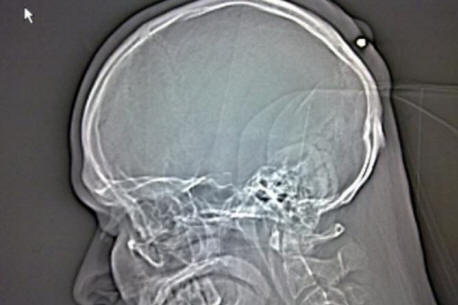

Позовавайки се на болницата, Autullo отказа да повярва в това лекарите му показаха: на рентгена беше ясно, че това осем сантиметров железен нокът, забит точно в черепа кутии от Данте. Преди линейката откарала Autullo в друга клиника на операция, Данте публикува снимка на това на страницата си във Facebook рентгенова снимка.